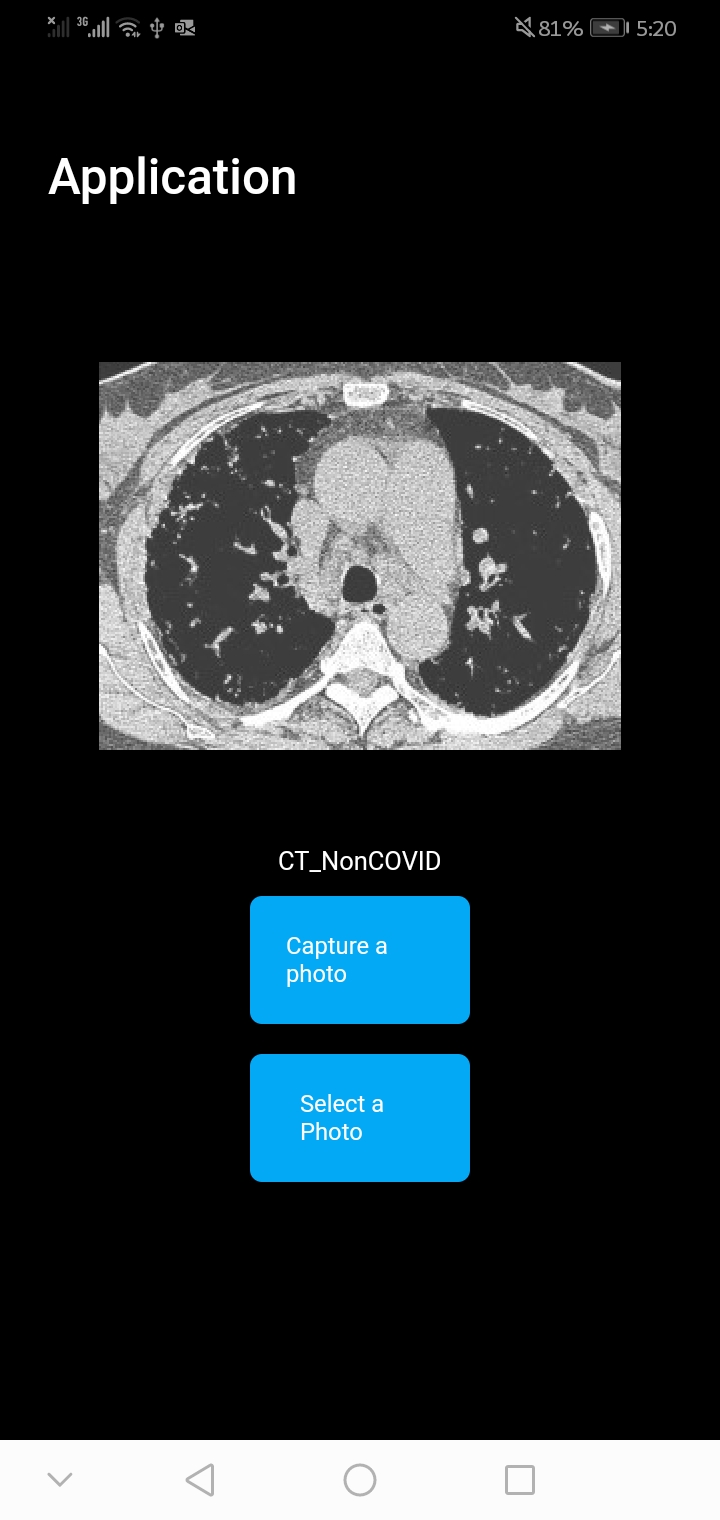

After this step, we have a label file and a model with metadata. Specify appropriate application development (Section, 2.6) used flutter image classification template. Examples of the final application at work can be seen in Figures 7(a) and 7(b).

In execution and final considerations (Step 7, section 2.7), we considered the first 5 images from both (CT_COVID and CT_nonCOVID) categories for the final testing on mobile phone, and those images were not part of model training/testing. We tested the model performance on the mobile phone in real-time, and the final accuracy was 0.6, which means the model cannot be deployed, but the performance increased to 0.80 percent when images were loaded from the gallery (Flutter App).